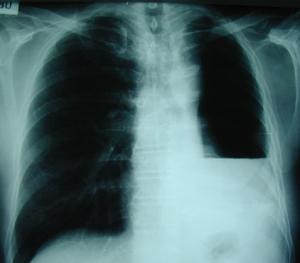

Εικόνα 2

Μετεγχειρητική ακτινογραφία θώρακος, ένας μήνας μετά από την πνευμονεκτομή. Στο αριστερό ημιθωράκιο υπάρχει υδραερικό επίπεδο, που δηλώνει την αναμενόμενη συλλογή υγρού και την έναρξη της απορρόφησης του αέρα από τον χώρο της πνευμονεκτομής. Ο χρόνος που χρειάζεται για να γεμίσει η κοιλότητα της πνευμονεκτομής με υγρό κυμαίνεται από τρεις εβδομάδες έως επτά μήνες, με μέσο όρο 3,9 μήνες.